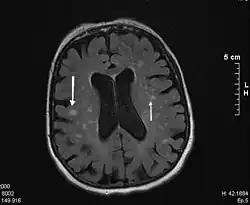

La demencia vascular (también, demencia multiinfarto o trastorno neurocognitivo vascular) es la segunda causa de demencia en adultos, después de la enfermedad de Alzheimer.[1] El término hace referencia a un grupo de enfermedades que provocan lesiones en el cerebro por daño en los vasos sanguíneos del mismo. La causa más frecuente es la arterioesclerosis. El diagnóstico temprano es importante para corregir los factores de riesgo implicados y evitar en lo posible el avance de la enfermedad.

Común a los tres protocolos de diagnóstico se encuentra la característica clave de que debe encontrarse algún grado de deterioro cognitivo, acompañado de evidencia de alguna contribución de tipo vascular a dicho deterioro (que puede provenir de cualquier combinación entre historia clínica, examen físico, perfil cognitivo y evaluación diagnóstica, incluyendo neuroimagen).[cita requerida]

- Requerimiento de evidencia de patología cerebrovascular mediante neuroimagen.

Los signos y síntomas neurológicos (por ejemplo exageración de los reflejos tendinosos profundos, respuesta de la extensión plantar, parálisis seudobulbar, anomalías en la marcha, debilidad de una extremidad) o las pruebas de laboratorio sugerentes de la presencia de una enfermedad cerebrovascular se estiman etiológicamente relacionadas con la alteración (por ejemplo, infartos múltiples que implican al córtex y a la sustancia blanca acompañante).[cita requerida]